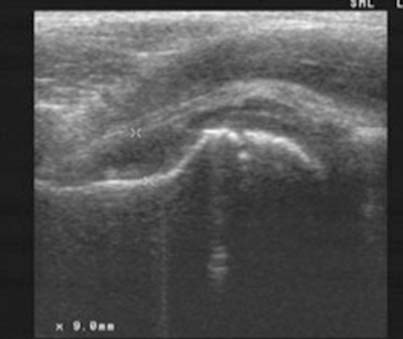

Διάγνωση. Ο υπερηχογραφικός έλεγχος απεικονίζει την ενδαρθρική συλλογή, χωρίς πάχυνση του υμένα, με φυσιολογικό ύψος και ομαλή παρυφή της χόνδρινης κεφαλής.

Εικόνα ενδαρθρικής συλλογής σε υμενίτιδα ισχίου, στον υπερηχογραφικό έλεγχο.